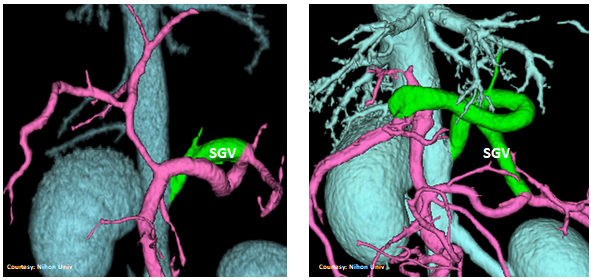

Does the SHORT GASTRIC VEIN (SGV) contribute blood to the shunt?

WEISSE 2022

“LGC +RGV +SGV”

Left Gastro-Caval Shunt with Right Gastric Vein and Short Gastric Vein contributions

Courtesy: Nihon Univ